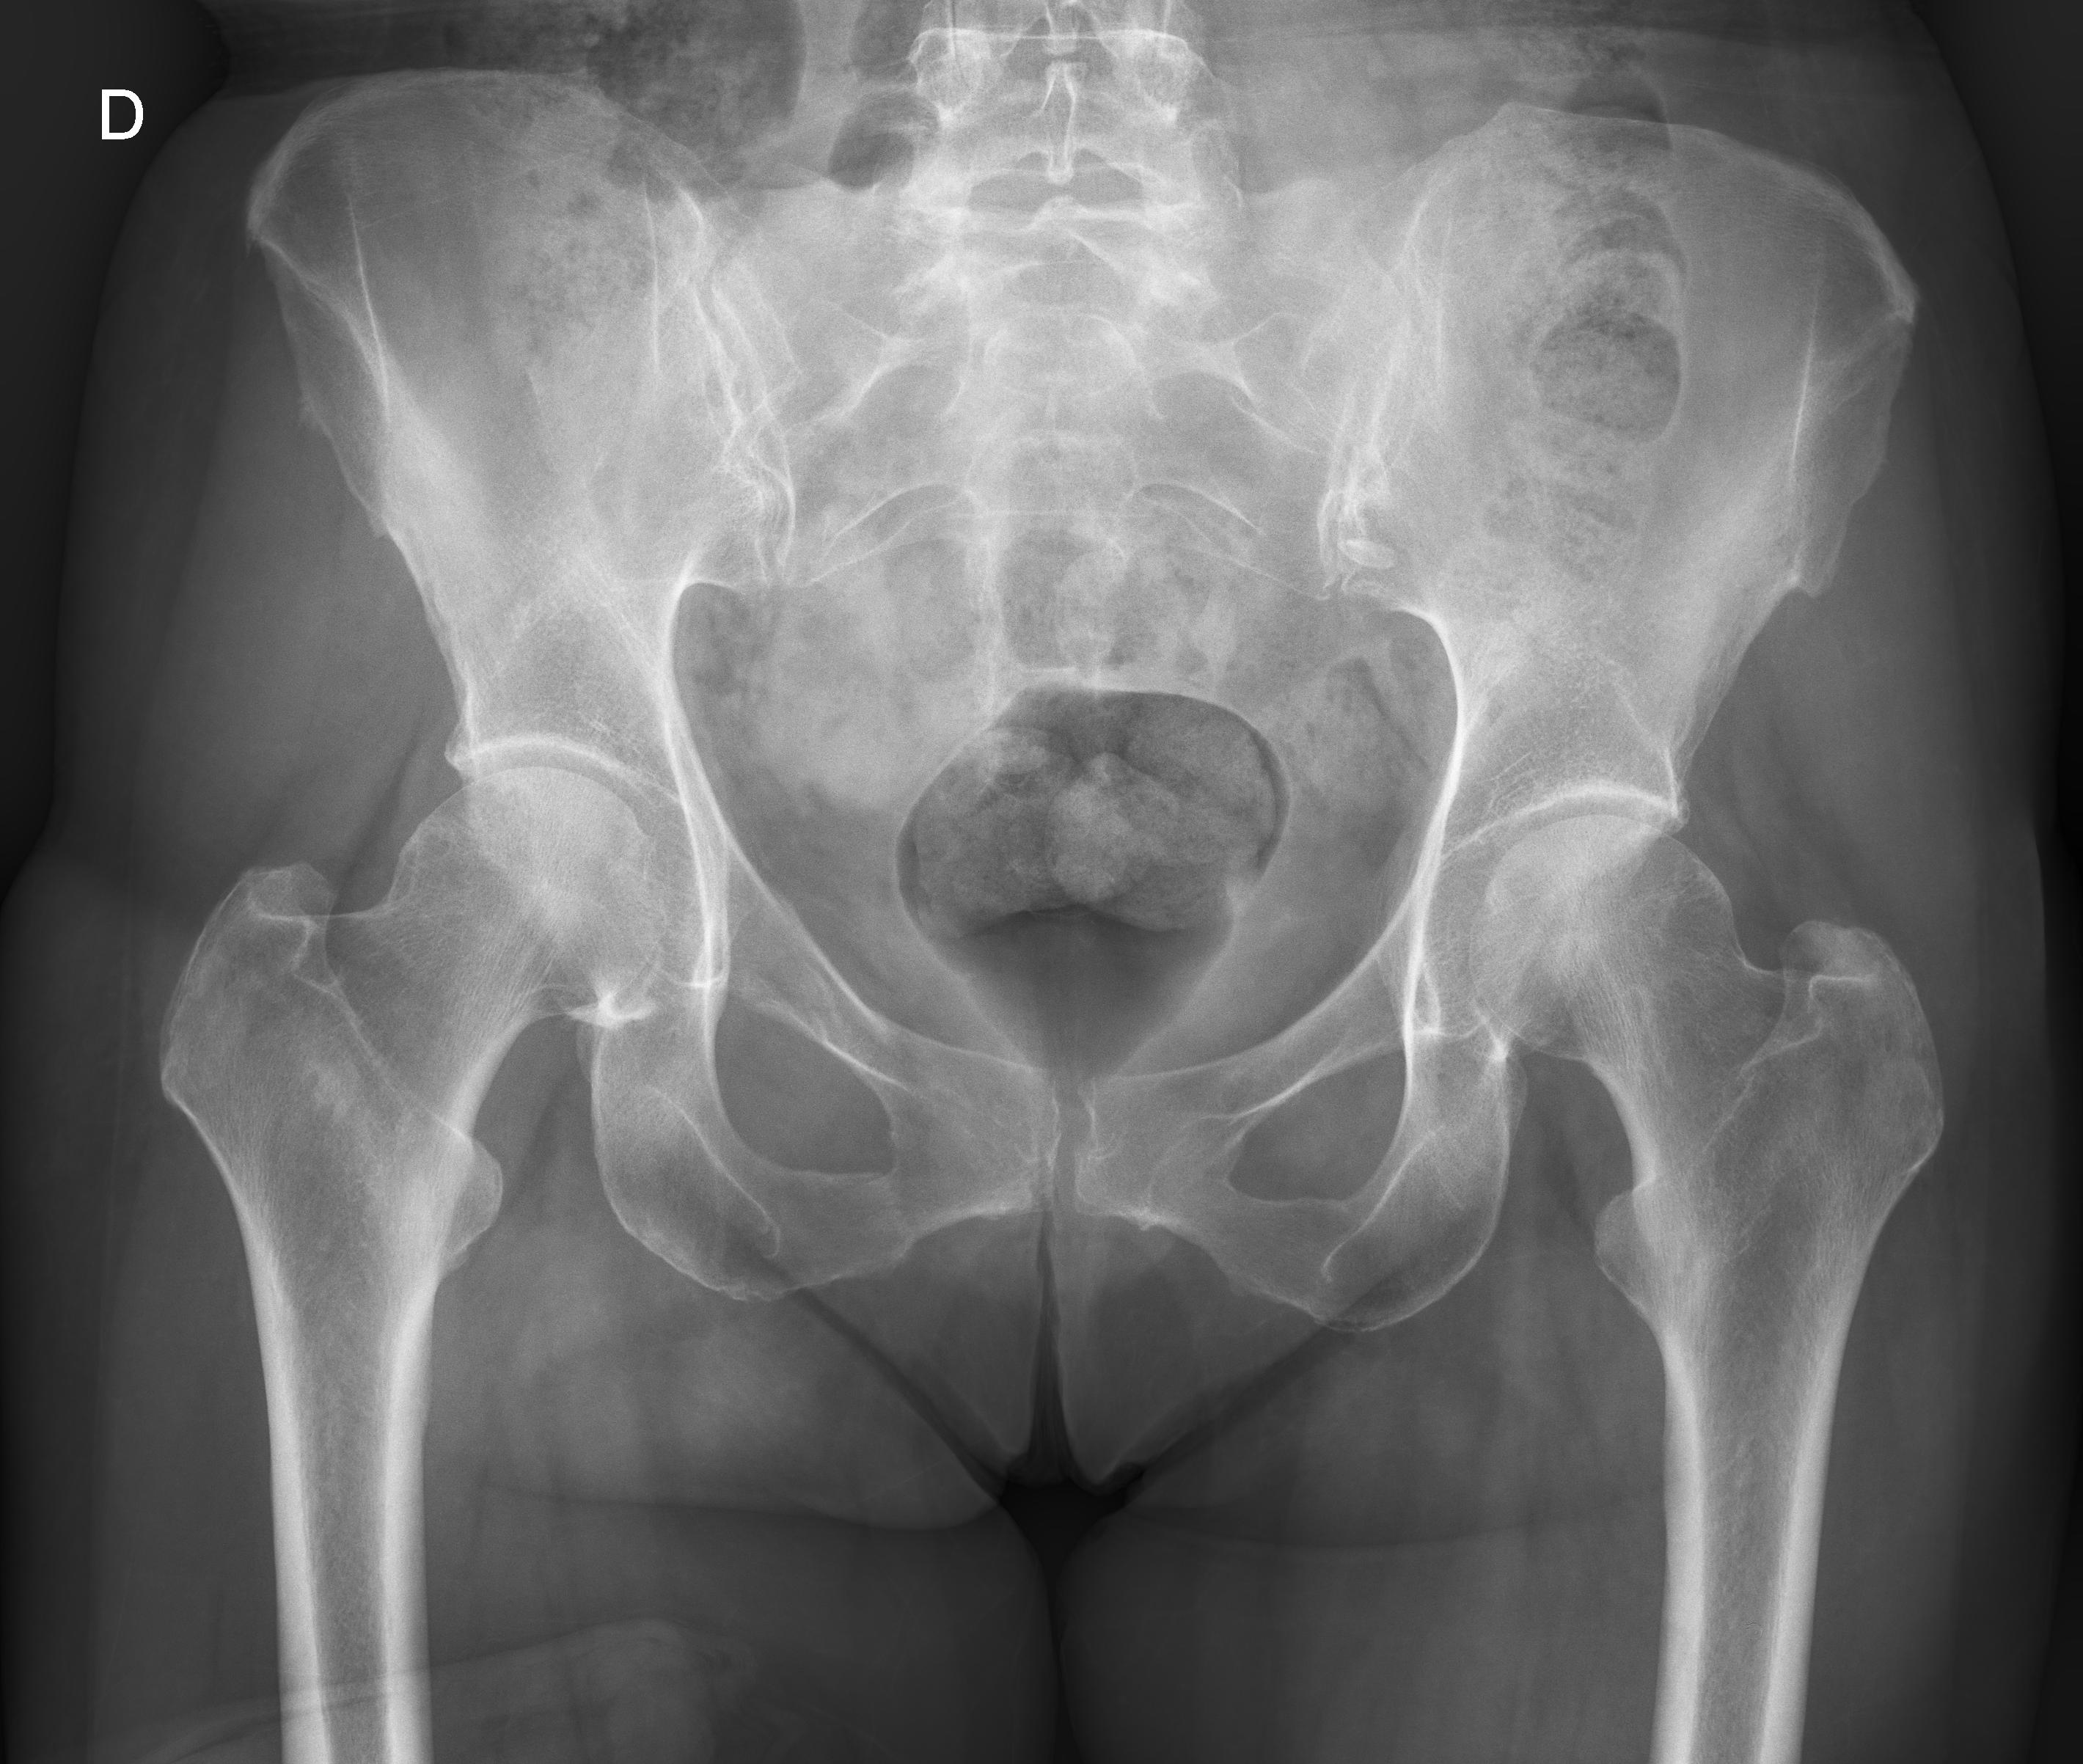

1 Cadera der.